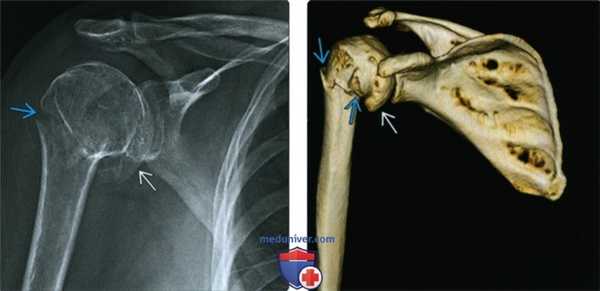

(Слева) На передне-задней рентгенограмме определяется перелом хирургической шейки. Сложно сказать, является ли медиальный край головки плечевой кости отдельным отломком перелома или остеофитом.

(Справа) На 3D КГ с реконструкцией у этого же пациента определяется перелом хирургической шейки и подтверждается, что медиальный край является большим остеофитом.